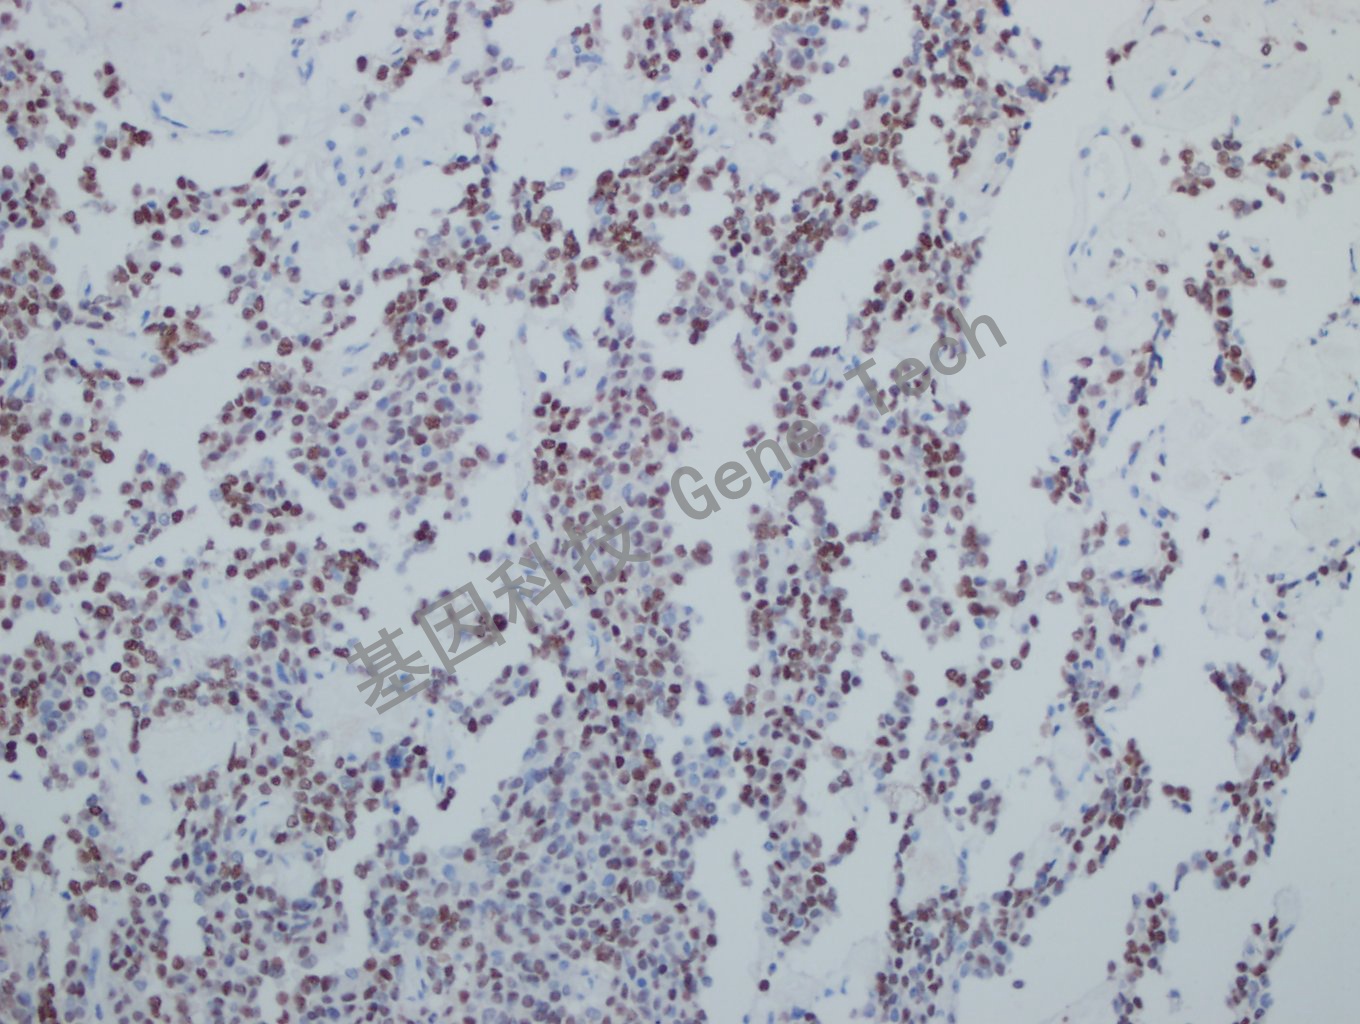

垂体瘤石蜡切片,用 PIT-1(GT2319)染色,细胞核阳性,DAB 显色。